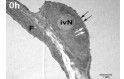

Migration neutrophiler Granulozyten in die verschiedenen Kompartimente der Lunge

Die chemokininduzierte Einwanderung neutrophiler Granulozyten in die Lunge ist ein zentraler pathophysiologischer Mechanismus im Rahmen des akuten Lungenversagens. Die zentrale Bedeutung von DARC für die Konzentration zirkulierender Chemokine impliziert eine mögliche Rolle bei der Entstehung des akuten Lungenversagens.